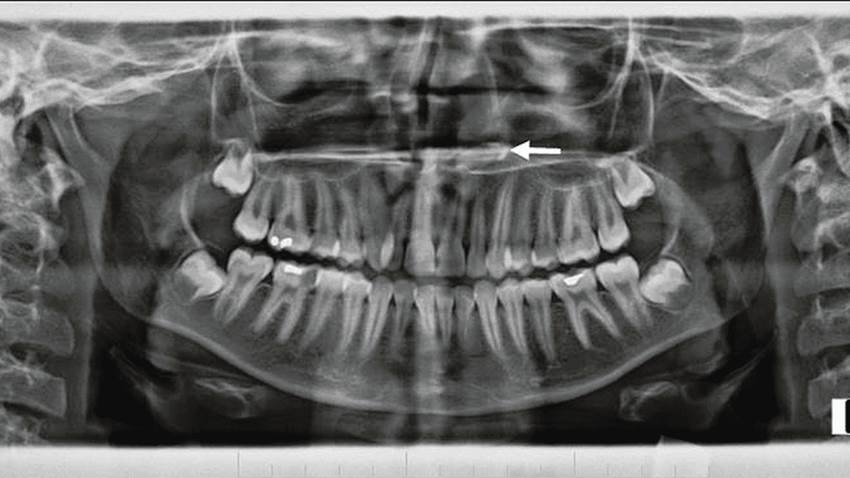

Raro de diente ectópico intranasal en mujer joven se registra en la literatura

Los dientes ectópicos que se presentan fuera de la cavidad oral pueden ser dientes deciduos, permanentes o supernumerarios, tal cual refleja su incide...